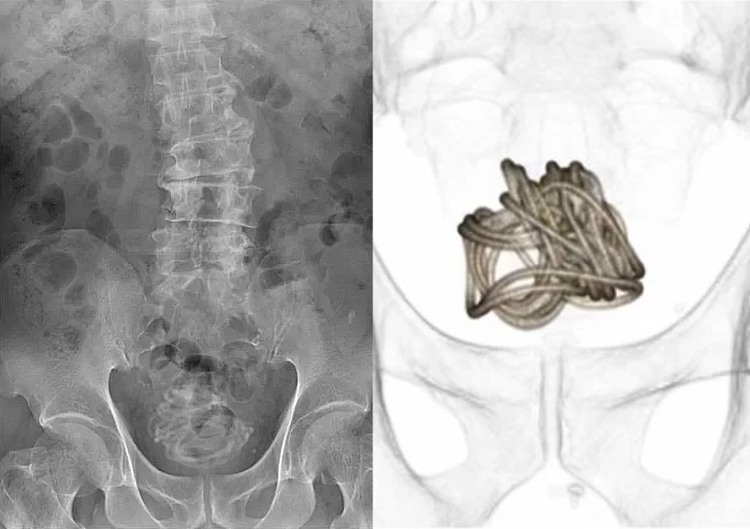

O homem foi até uma unidade hospitalar reclamando de dores no abdômen e com dificuldades para urinar. Ele fez um exame de imagem para verificar a origem do desconforto, então a equipe médica se assustou ao ver que a corda enrolada na bexiga do paciente. O paciente admitiu ter enfiado a corda pela uretra, mas não explicou o motivo.